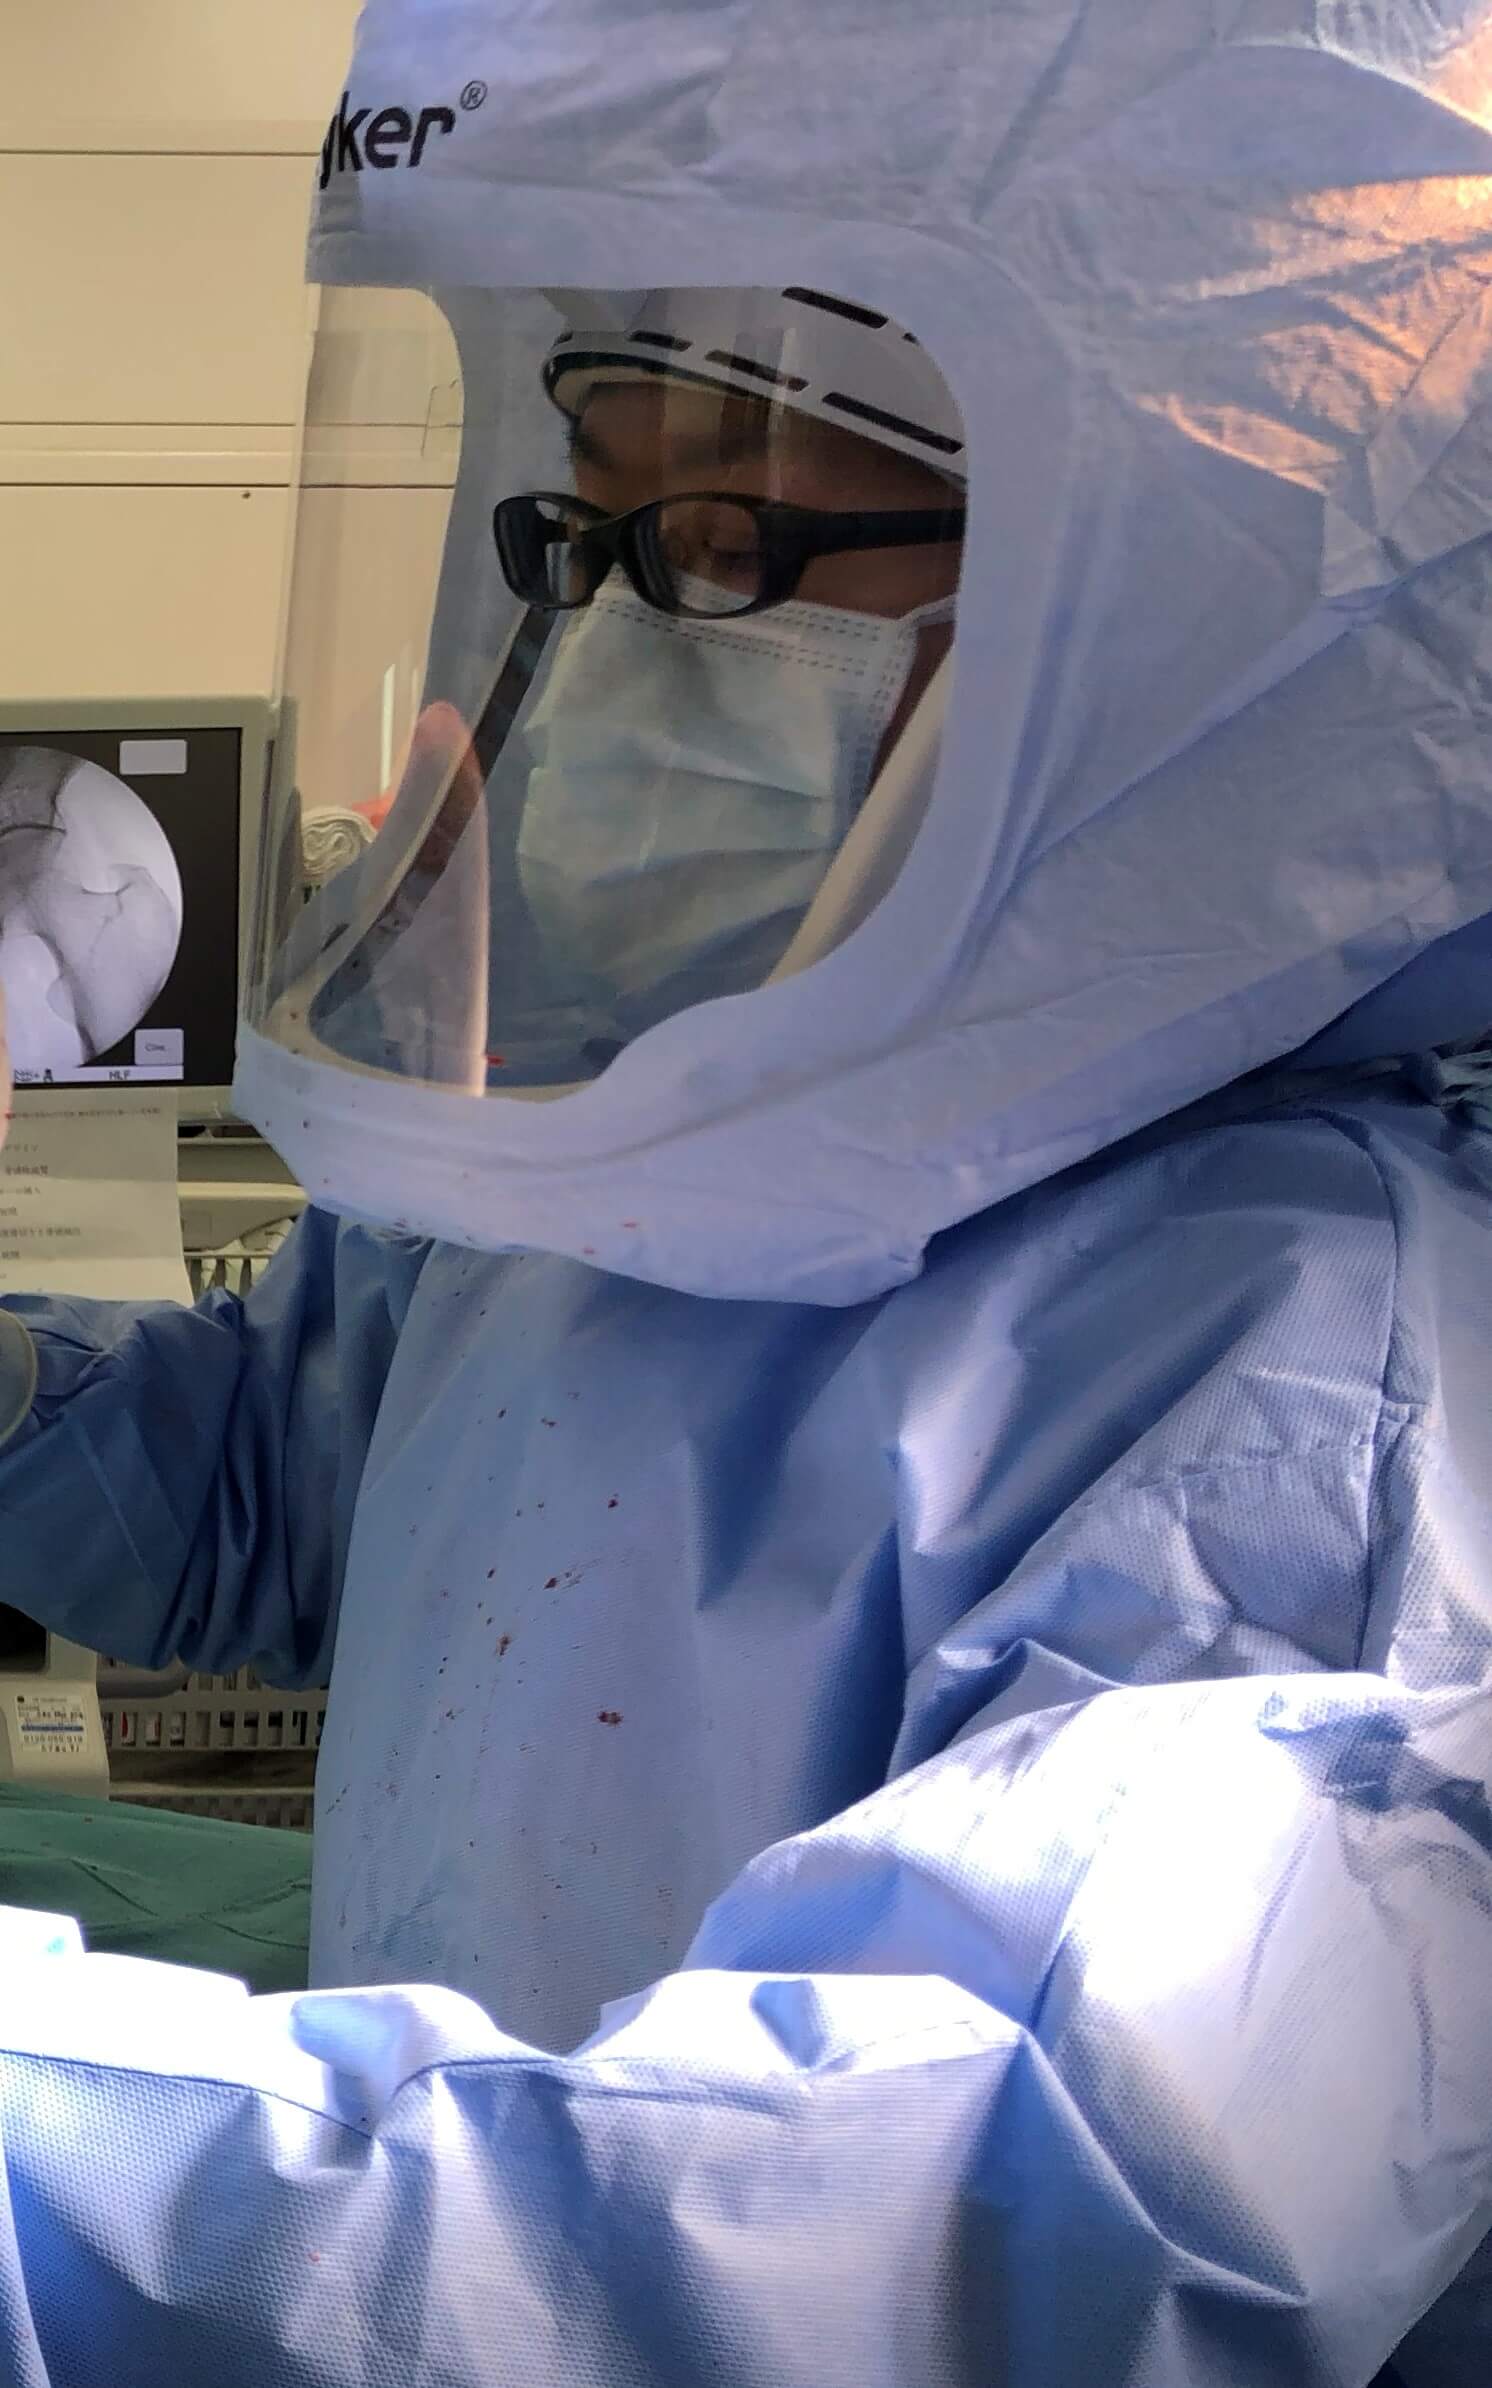

人工膝関節置換術を行うことによって

ただし、X脚の場合は

内側側副靭帯がゆるんでしまっている場合があるため

その場合には通常よりも拘束性が高い

人工膝関節のインプラントを使用します。